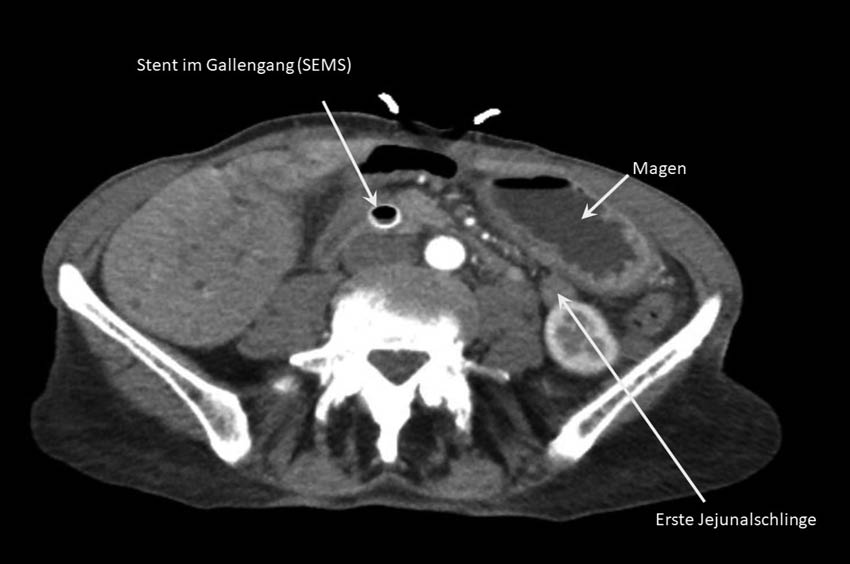

Eine 79-jährige Patientin mit bekanntem inoperablem Choledochuskarzinom litt an ausgeprägter Übelkeit, rezidivierendem Erbrechen und Völlegefühl bei Tumorinfiltration des Duodenums (Abbildung 5). Eine Ballondilatation der Duodenalstenose hatte keinen klinischen Erfolg gebracht.

Zur Linderung der Symptomatik wurde der Patientin als Alternative zur operativen Anlage einer GE sowie einer Ablauf-PEG die EUS-GE angeboten (Abbildung 6). Diese erfolgte in o. g. Technik komplikationslos. Bereits am Folgetag berichtete die Patientin eine deutliche Besserung der Symptome und konnte rasch mit dem Nahrungsaufbau beginnen. Die Patientin wurde zwei Tage nach dem Eingriff in die Häuslichkeit entlassen.